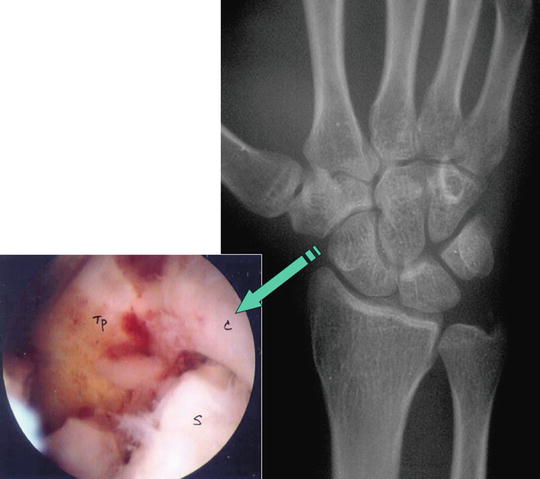

Arthroscopic Partial Wrist Fusion | Musculoskeletal Key

Figure 4 from Arthroscopic-Assisted Partial Wrist Arthrodesis …